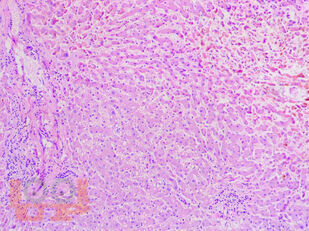

В учебном пособии представлен теоретический материал, перечень макропрепаратов и микропрепаратов, демонстрирующих типовые проявления патологических процессов. В цветных иллюстрациях и в описании микропрепаратов сделан акцент на наиболее важных гистологических изменениях, позволяющих на светооптическом уровне диагностировать и дифференцировать состояния, отклоняющиеся от нормы, в том числе с использованием различных гистологических окрасок. Пособие помогает выделить главные аспекты изучаемых патологических процессов, организовать и конкретизировать учебный процесс.